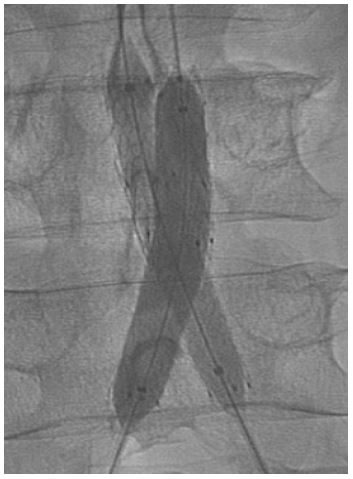

Male patient, 72 years, active smoker, with arterial hypertension, diabetes, and disabling bilateral inferior limbs claudication. The patient was submitted to endovascular surgery with an iliac kissing stent and implant of Wrapsody 9×50 mm at the right iliac common artery and Wrapsody 9×75 mm at the left common iliac artery, followed by post-dilatation with a catheter balloon. (Figure 4) The patient was discharged from the hospital first day post-operative and 1-month follow-up showed endoprosthesis patency with complete resolution of the previous symptoms.

Figure 4: Iliac kissing stent and implant of Wrapsody 9×50 mm at the right iliac common artery and Wrapsody 9×75 mm at the left common iliac artery.